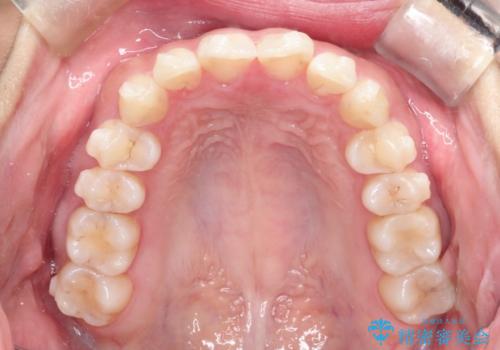

【インビザライン】翼状捻転+出っ歯を治したい

- 前歯の捻れと口元の突出を主訴に来院されました。

インビザラインを用いて上顎の遠心移動を行い、前歯を下げながら凸凹を綺麗に治すことができました。

歯を抜かない矯正治療を行う場合、口元は極端には変わりません。

今回は奥歯の遠心移動を行い、できる限り前歯を下げられるように治療を行いました。